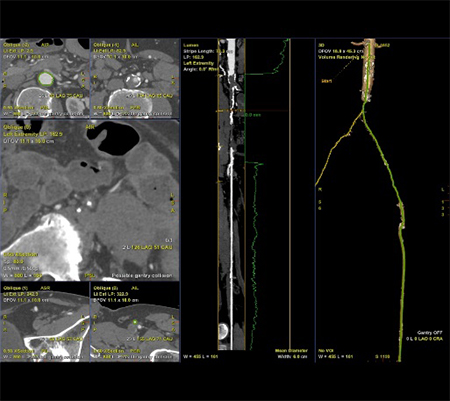

下肢血管における使用例を示す。術前CTAではAortic bifurcationからの完全閉塞となっていた(図5)。完全閉塞部分へのアプローチに対して難渋することが予測されたため、下肢血管解析結果を用いた3D Roadmap使用を検討した。AWVS7は下肢血管解析ソフトを用いることで自動的に血管、骨(術中3D Roadmapの位置合わせ用)を作成する(図6)。狭窄症例などでは自動作成された血管3Dを透視と重ねる3D Roadmapが治療サポートになるが、CTO症例ではワイヤーを進めるためのラインの有用性に着目し、CTO部分を含めた血管センターラインを作成した(図7)。血管センターラインはワイヤーを進める際のReferenceとして有用(図8)であり、3次元での位置情報を有したラインであるため、角度変更やFOV変更、テーブル移動にも追従する。また治療前のDSAでは表示されないTrue面を表示させることは、手技を進めていく中で有用なサポートになったと当院医師よりフィードバックがあった。3D Roadmapは術中にボリュームレンダリングの透過度変更や表示の有無、センターラインの表示の有無も変更可能である。CTO部分を通過させている場合にはセンターラインの表示、通過後のバルーン拡張やステント留置時にセンターラインではなく、ボリュームレンダリング表示による病変部の逆描出など場面に合わせた変更を可能としている。また任意5倍までのデジタルズーム表示機能もあり、今後の症例で使っていきたい。

IGS740_SendaiTokusyukai_07.jpg図7 CTO部分を含めた血管解析によるセンターラインとLumen View表示